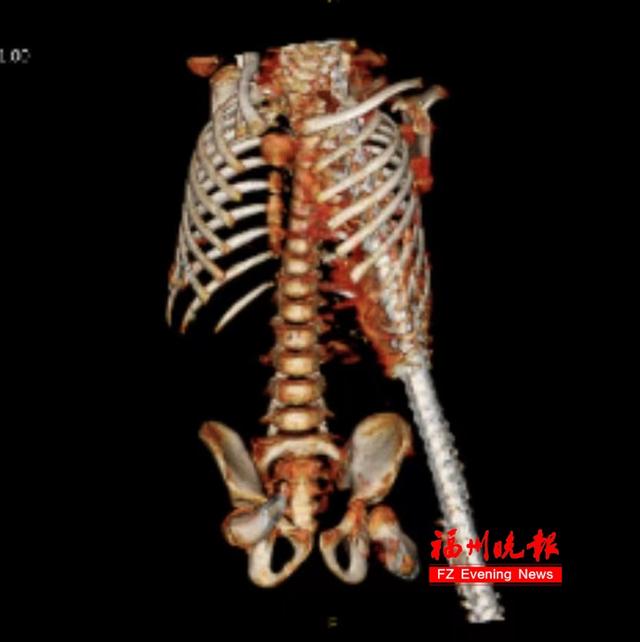

被一根一米多长、锈迹斑斑的钢筋

斜向贯穿了腹部、胸腔和肩部

“那根钢筋,从左上腹插入,造成胃被捅了前后两个大口,大肠和小肠有不同程度撕裂,左肝有一个裂口并疝入胸腔,左肺也有破裂出血。

同时,钢筋还紧贴着心脏后方和左肺血管,最后从左颈肩部穿出。此外,他的胸腹腔内还残留着大量血性积液及铁锈。”

随着钢筋被慢慢抽出,没有出现活动性出血